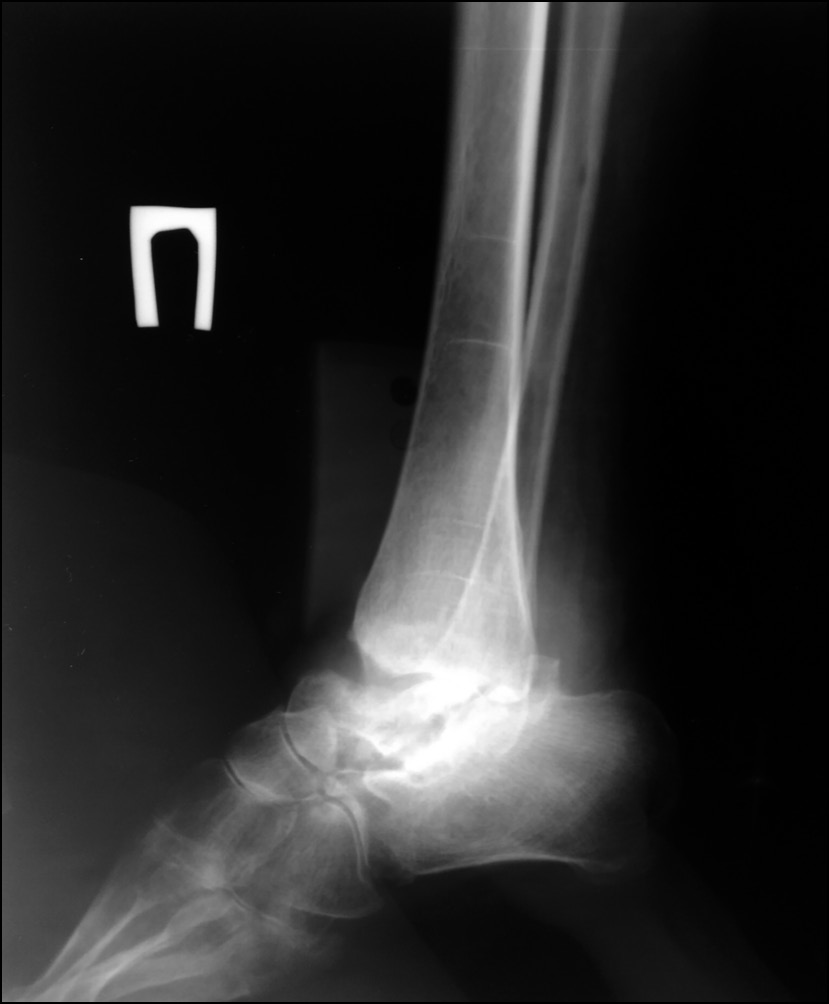

Рис. 9. Рентгенограмма в передне-задней проекции после окончания коррекции варусной деформации.

Fig. 9. X-ray image in anterior-posterior projection after correction of varus deformity.

Через 10 дней после операции начата этапная дозированная дистракция в зоне остеотомии на переднезадних стержнях, соответствующих оси большеберцовой кости, 0,75 мм/сут, на медиальном стержне — 1,0 мм/сут. Каждые 2 недели проводилось рентгенографическое исследование для оценки степени коррекции деформации и контроля удлинения. После коррекции углового смещения (рис. 9) скорость дистракции на трёх стержнях была одинаковой — 0,75 мм/сут. Через 8 недель после начала дистракции, когда диастаз между костными фрагментами составлял 40 мм, была достигнута компенсация укорочения и деформации конечности, дистракция была остановлена. К этому времени отмечались начальные признаки формирования костного регенерата, рентгенологические признаки снижения МПКТ оставались на прежнем уровне. Маркеры костного метаболизма не выходили за пределы референса — остеокальцин 34,76 нг/мл (11–43), С-концевой телопептид коллагена I типа — 0,346 нг/мл (0,3–0,57). После коррекции дефицита витамина D (приём колекальциферола 50 000 МЕ еженедельно в течение 8 недель внутрь, далее 2000 МЕ ежедневно внутрь) уровень ПТГ нормализовался и составил 61,7 пг/мл (15–65).

В последующем рентген-контроль осуществлялся ежемесячно. Плотность костного регенерата увеличивалась, однако отмечалась отрицательная динамика МПКТ. Через 4 месяца после операции обнаружены признаки гипотрофии регенерата — его сужение и извитая линия пониженной плотности, расположенная поперечно, ограниченная зоной с повышенной плотностью костной ткани (склероз) на уровне средней части регенерата; это также сопровождалось общими признаками сниженной МПКТ (рис. 10).

Рис. 10. Рентгенограмма в косой проекции с признаками гипотрофии регенерата.

Fig. 10. X-ray image in oblique projection with signs of regenerate malnutrition.

Рис. 11. Рентгенограммы после демонтажа аппарата Илизарова.

Fig. 11. X-ray images after dismantling of Ilizarov device.

Через 4 месяца лечения терипаратидом отмечено четырёхкратное увеличение маркера костеобразования (остеокальцина) — 133,1 нг/мл (11–43). По результатам денситометрии отмечено увеличение МПКТ на 9,7% в лучевой кости и до 5% — в бедренной кости. По рентгенологическим данным выявлена положительная динамика в отношении формирования костного регенерата: увеличение плотности, однородности, снижение проявлений общего снижения МПКТ. Ещё через 2 месяца отмечалось формирование кортикальной пластинки на всём протяжении регенерата, после чего принято решение о демонтаже аппарата Илизарова, общий срок применения которого составил 10 месяцев (рис. 11).